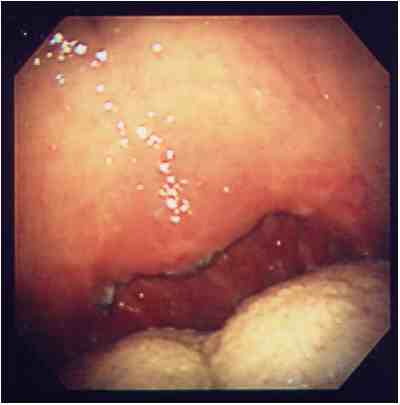

無呼吸の原因と考えられるポリープ様声帯に対し,喉頭微細手術を行い,

軟口蓋低位と狭い口峡に対し、UPPPを行った例。

手術前の声帯手術後の声帯

気道が広くなっているのがわかります。

手術前の咽頭手術後の咽頭

のどの奥が広くなっているのがわかります。